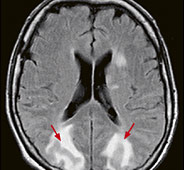

Abb. 3

Kopfschmerzen und Sehstörungen bei krisenhafter Blutdruckerhöhung. Die Signalveränderungen der MRI-Untersuchung zeigen die charakteristischen, reversiblen Wassereinlagerungen in beiden Hinterhauptslappen (Pfeile).